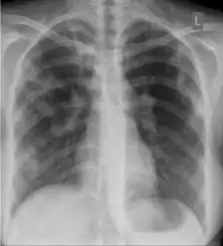

5. Hilar or mediastinal lymphadenopathy (bihilar lymphadenopathy) - Enlargement of lymph nodes in one or both hila or within the mediastinum, with or without associated atelectasis or consolidation.

Chest x-ray showing bilateral hilar adenopathy of primary pulmonary TB